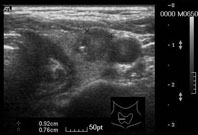

檢查甲狀腺結節最重要的工具是超音波,現代超音波的發展到比0.2公分大的結節都可以檢查出來。超音波可以用來幫忙分辨甲狀腺結節的良惡性。在超音波下(圖二)如果出現微小鈣化,前後徑大於左右徑,周圍界線不清或是異常的血流型態,會懷疑是惡性甲狀腺癌,於是醫師會在超音波即時引導下,用細小的針頭,穿刺抽取結節中的細胞化驗,以確定診斷。至於結節大小則與良惡性沒有相關。

圖二、高解析耳鼻頭頸軟組織超音波可以準確的發現甲狀腺癌,圖為不到一公分大的甲狀腺癌於超音波下的典型表現